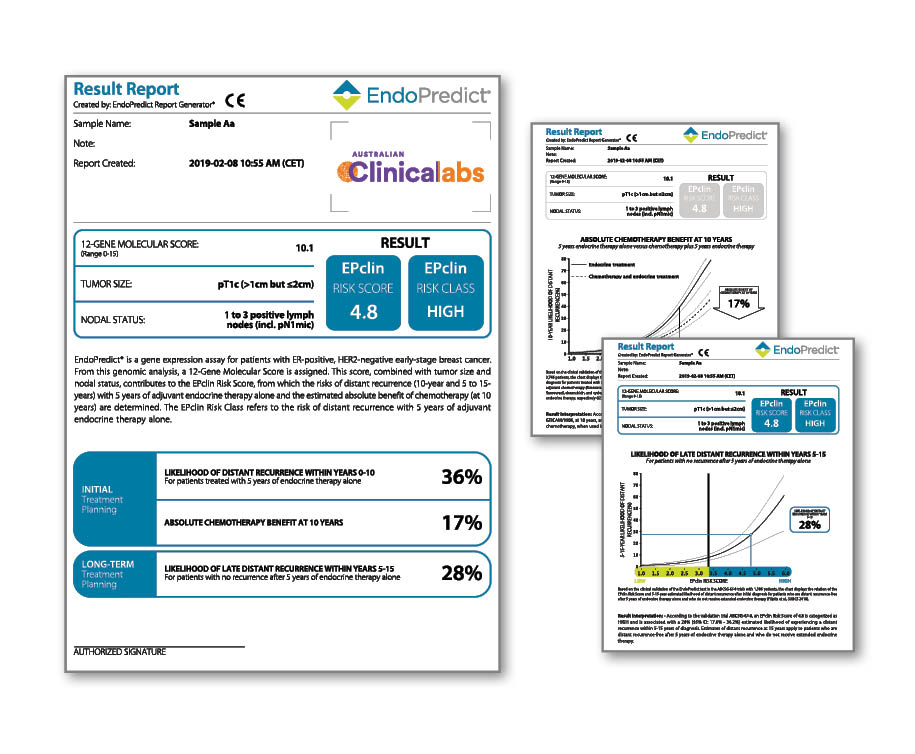

An advanced gene expression test for predicting the risk of distant recurrence in early-stage primary breast cancer.

EndoPredict, available at Clinical Labs, is the only prognostic test that provides insights into the risk of breast cancer recurrence, the benefits of chemotherapy and the suitability for extended endocrine therapy in women with ER+, HER2- primary breast cancer.

EndoPredict is a second-generation gene expression test for superior prognostic power and is now partially Medicare rebatable.

What does EndoPredict report?